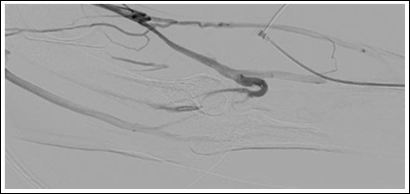

We chose a retrograde access to the cephalic vein. Catheteter angiography confirmed the ultrasound test results (Figure 1). Out flow of the cephalic vein was through basilic vein, cephalic vein of the upper arm and deep venous system in the cubital fossa via drainage through the perforating vein (Figure 2). We performed a balloon angioplasty of the arteriovenous fistula with a plain balloon (4 mm) at the end of the procedure.

Figure 2: Angiogram showing the perforating vein (à).

Catheter angiography shows vascular anatomy of the fistula with out flow obstruction at the upper arm cephalicvein (Figure 3) and well-developed collaterals (Figures 1 and 4). Troubleshooting was not such as adequate as we did appreciate preexisting problems in this case. Figure 1 demonstrates primary flow is drained through the collateral in the basilic system. Figure 2 shows inadequate drainage into the deep venous system through elbow perforator with lesions in upper arm cephalic vein and non-visualization of median cubital vein.